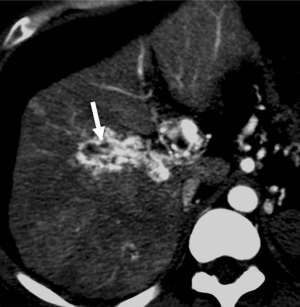

THED

THED indicate transient increased attenuation or signal intensity differences during the HAP, which return to normal or near-normal in the portal venous phase (PVP) and equilibrium phase. It typically manifests as a peripheral, wedge or cone shaped area with a straight margin, and contains normal vessels (Figure 3). THED usually occur in functional HAPS (transsinusoidal shunts and transplexal shunts) caused by decreased portal or hepatic venous flow due to contrast material passage from the high-pressure arterial blood into a low-pressure portal vein branch, thus enhancing a focal area of the liver before the adjacent parenchyma is enhanced through flow from the normal portal venous system (18,19).